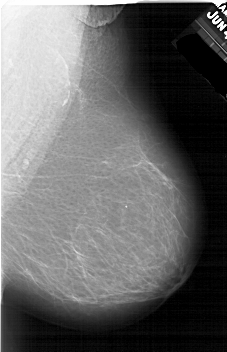

A_1639_1.RIGHT_CC

RIGHT_CC LINES 6871 PIXELS_PER_LINE 3946 BITS_PER_PIXEL 12 RESOLUTION 43.5 NON_OVERLAY